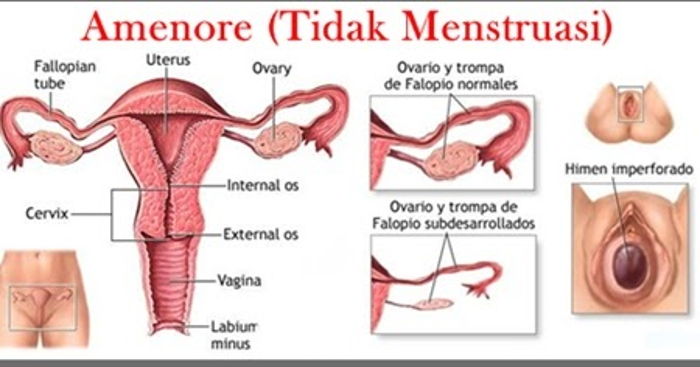

Hanımlarımızı oldukça tedirgin eden klinik tablolardan birisi de adet

görememe yani tibbi ismiyle amenore’dir.

Bir kız çocuğu ,14 Yaşına geldiği halde,memelerde büyüme ve

gelişme olmaması, veya tüylenme gibi ikincil cinsiyet karekterlerinin

gelişmemesi veya 16 yaşına gelmesine rağmen,ilk adetin görülmemesi

veya normal adetlerini gören kadında 3 ay üstüste adet görülmemesi

durumunda adet görememe veya amenore durumundan söz edilir.16

yaşına kadar hiç adet görememe durumuna ‘primer amenore’,adet gören

kadında adetlerin kesilmesine ise ‘sekonder amenore’ denilmektedir.

Daha iyi anlaşılması için,amenore denilen adet görememe

durumlarını şu şekilde maddeler halinde özetleyebiliriz :

gelişim bozuklukları ; doğumsal olarak rahim,tüpler ve vajenin

üst kısmının olmaması halidir,yumurtalıklar normal olduğu halde,adet

yoktur.

olmasına rağmen,dış görünüşleri kadın gibidir.

gonodal agenezis ; kişide yumurtalıklar gelişmemiştir.